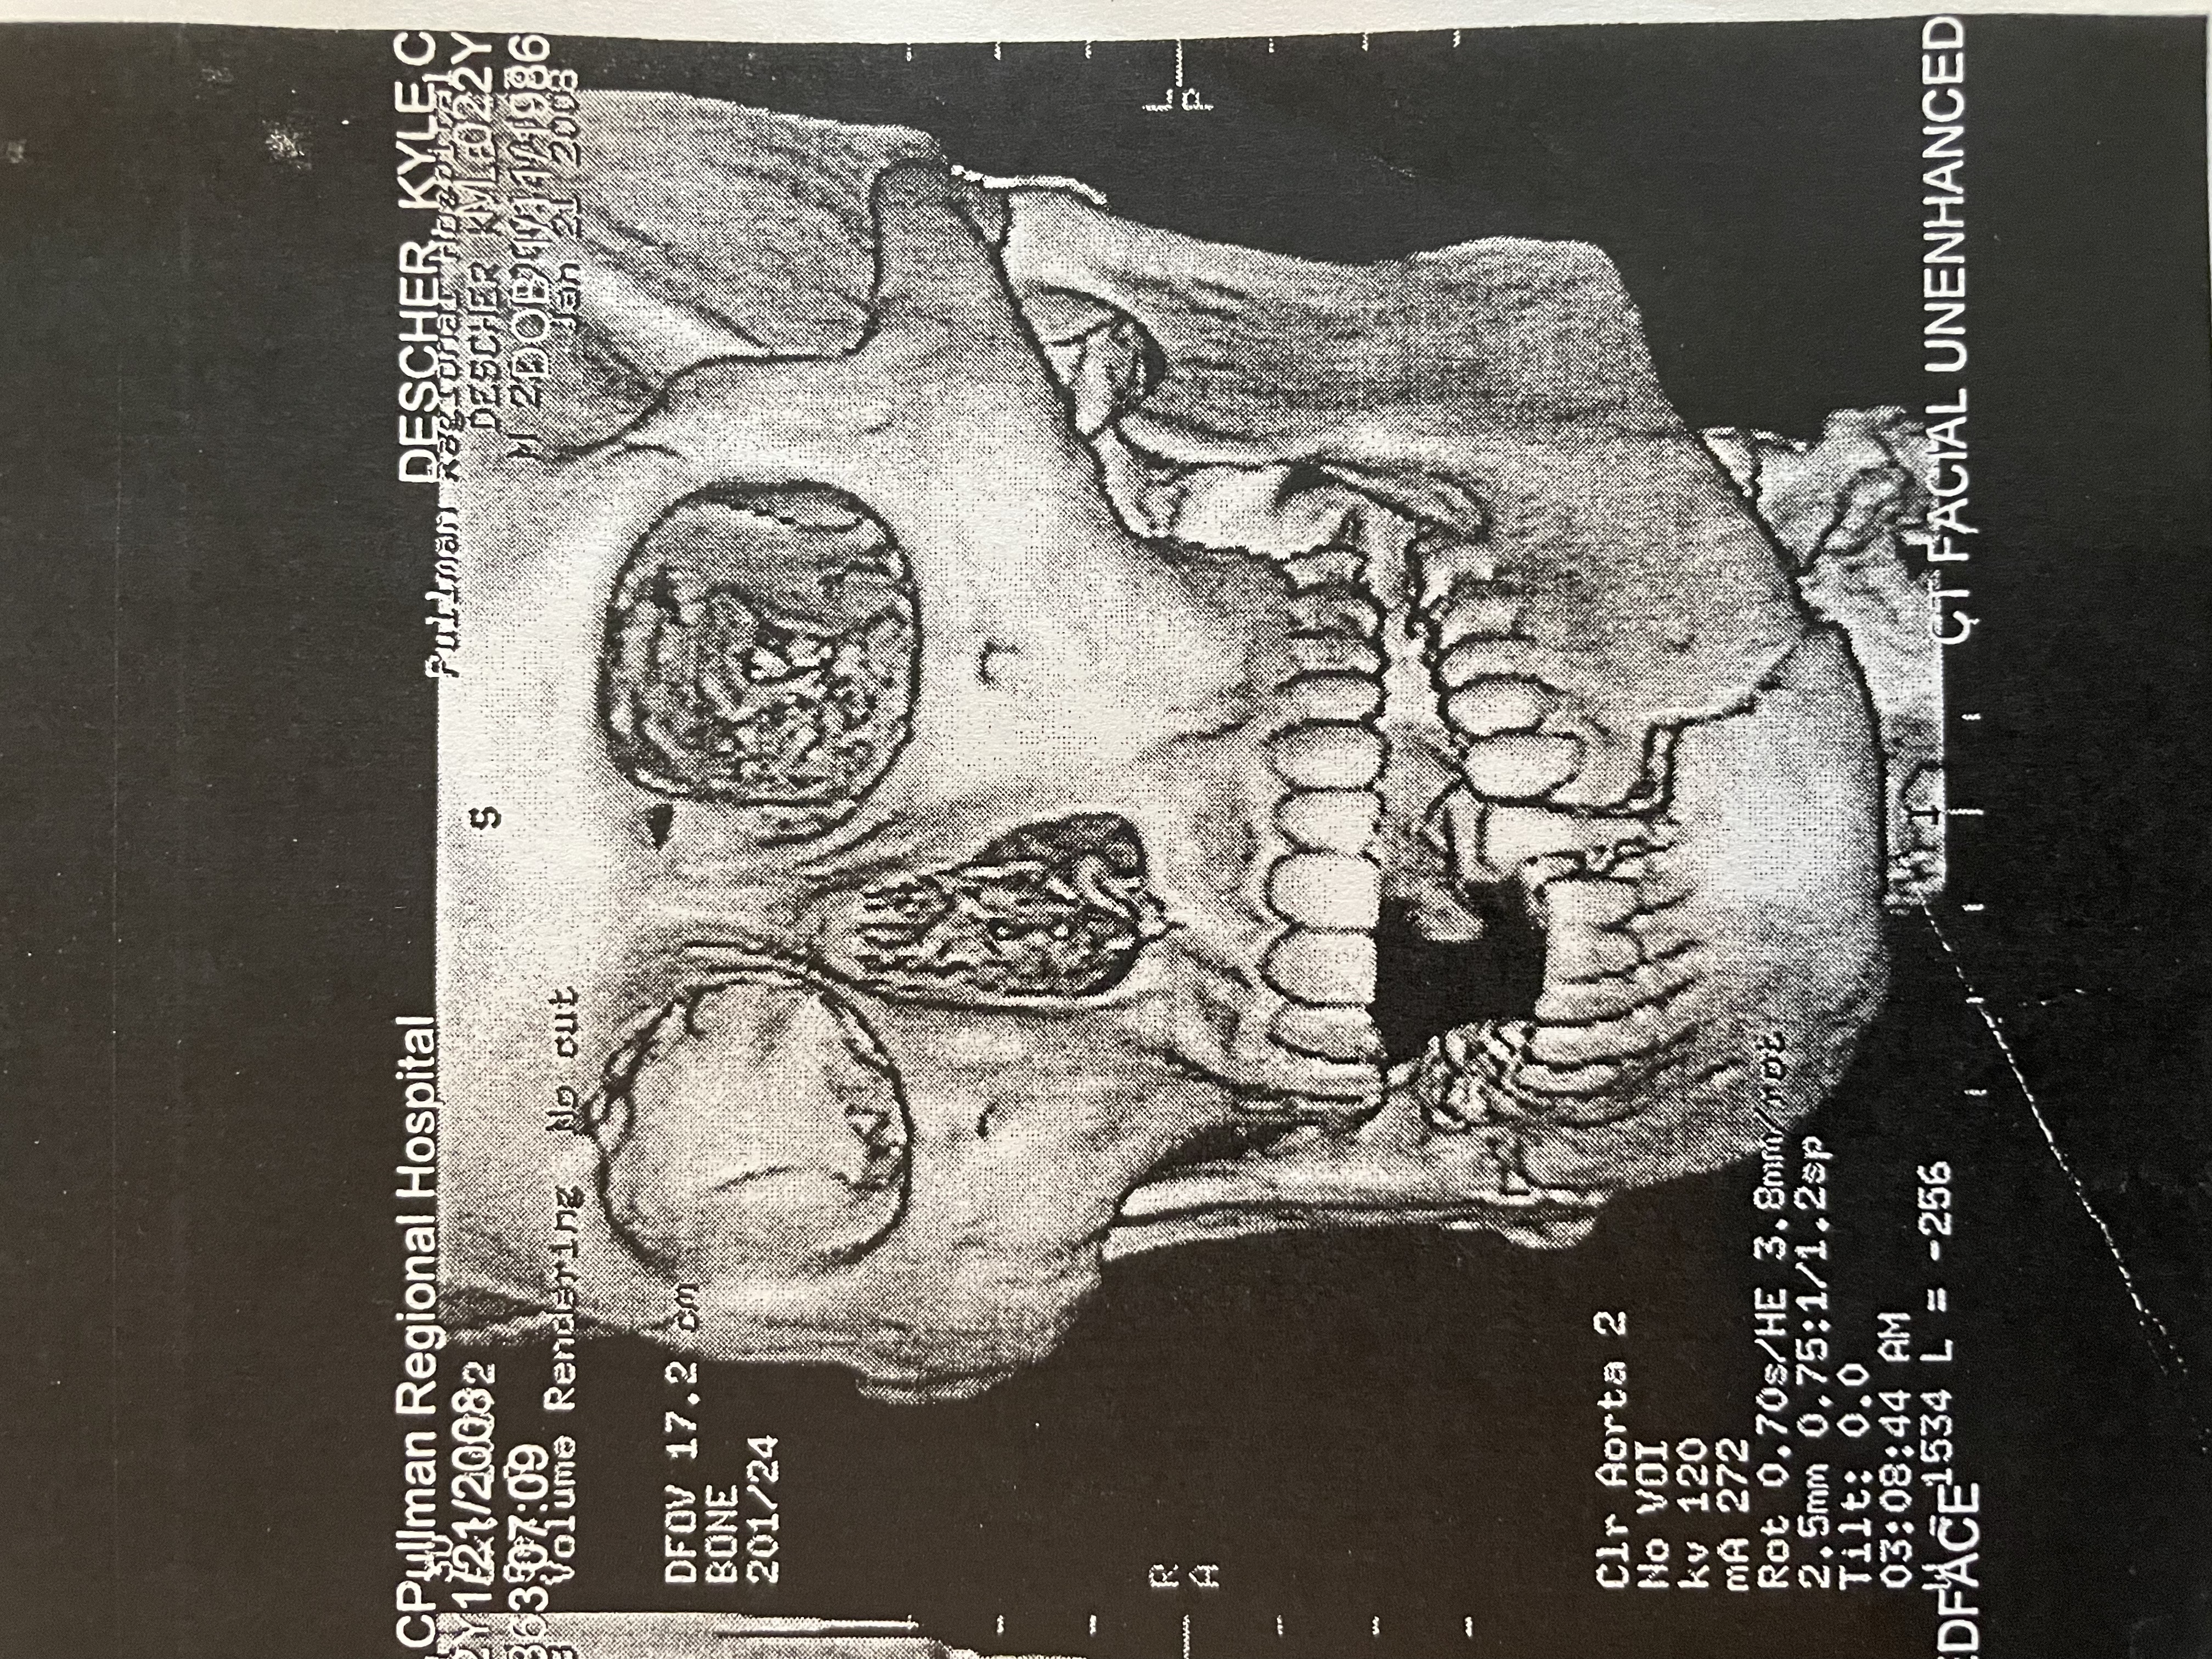

In 2008, my Senior year of college, a violent racist attack shattered my jaw in two places. Emergency reconstructive surgery. Three titanium plates. Three months with my jaw wired shut.